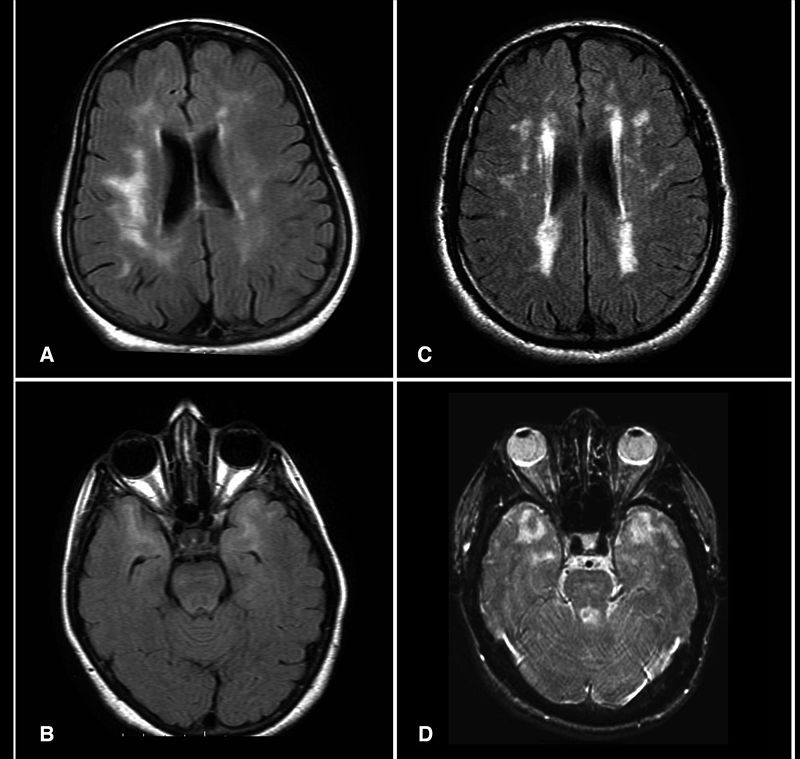

Ischemic Stroke

An ischemic stroke can cause regional ischemia that causes focal neurologic impairments that continue longer than 24 hours.

Symptoms of ischemic stroke depend on the region of brain involvement.

Histologic findings (if obtained) for strokes show:

- An early microscopic observation is an eosinophilic alteration in the cytoplasm of neurons (red neurons) (12 hours after infarction)

- Coagulative necrosis (24 hours)

- Neutrophil infiltration (days 1-3)

- Microglial cell infiltration (days 4-7)

- Granulation tissue (weeks 2-3)

Liquefactive necrosis is the outcome of ischemic stroke.

Liquefactive necrosis results in the development of a cystic area filled with fluid that is encircled by gliosis.